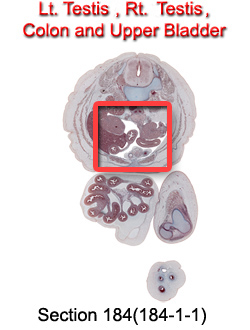

Tissue

Testes, Colon and Upper Bladder

Carnegie Embryo #9226

184-01-01